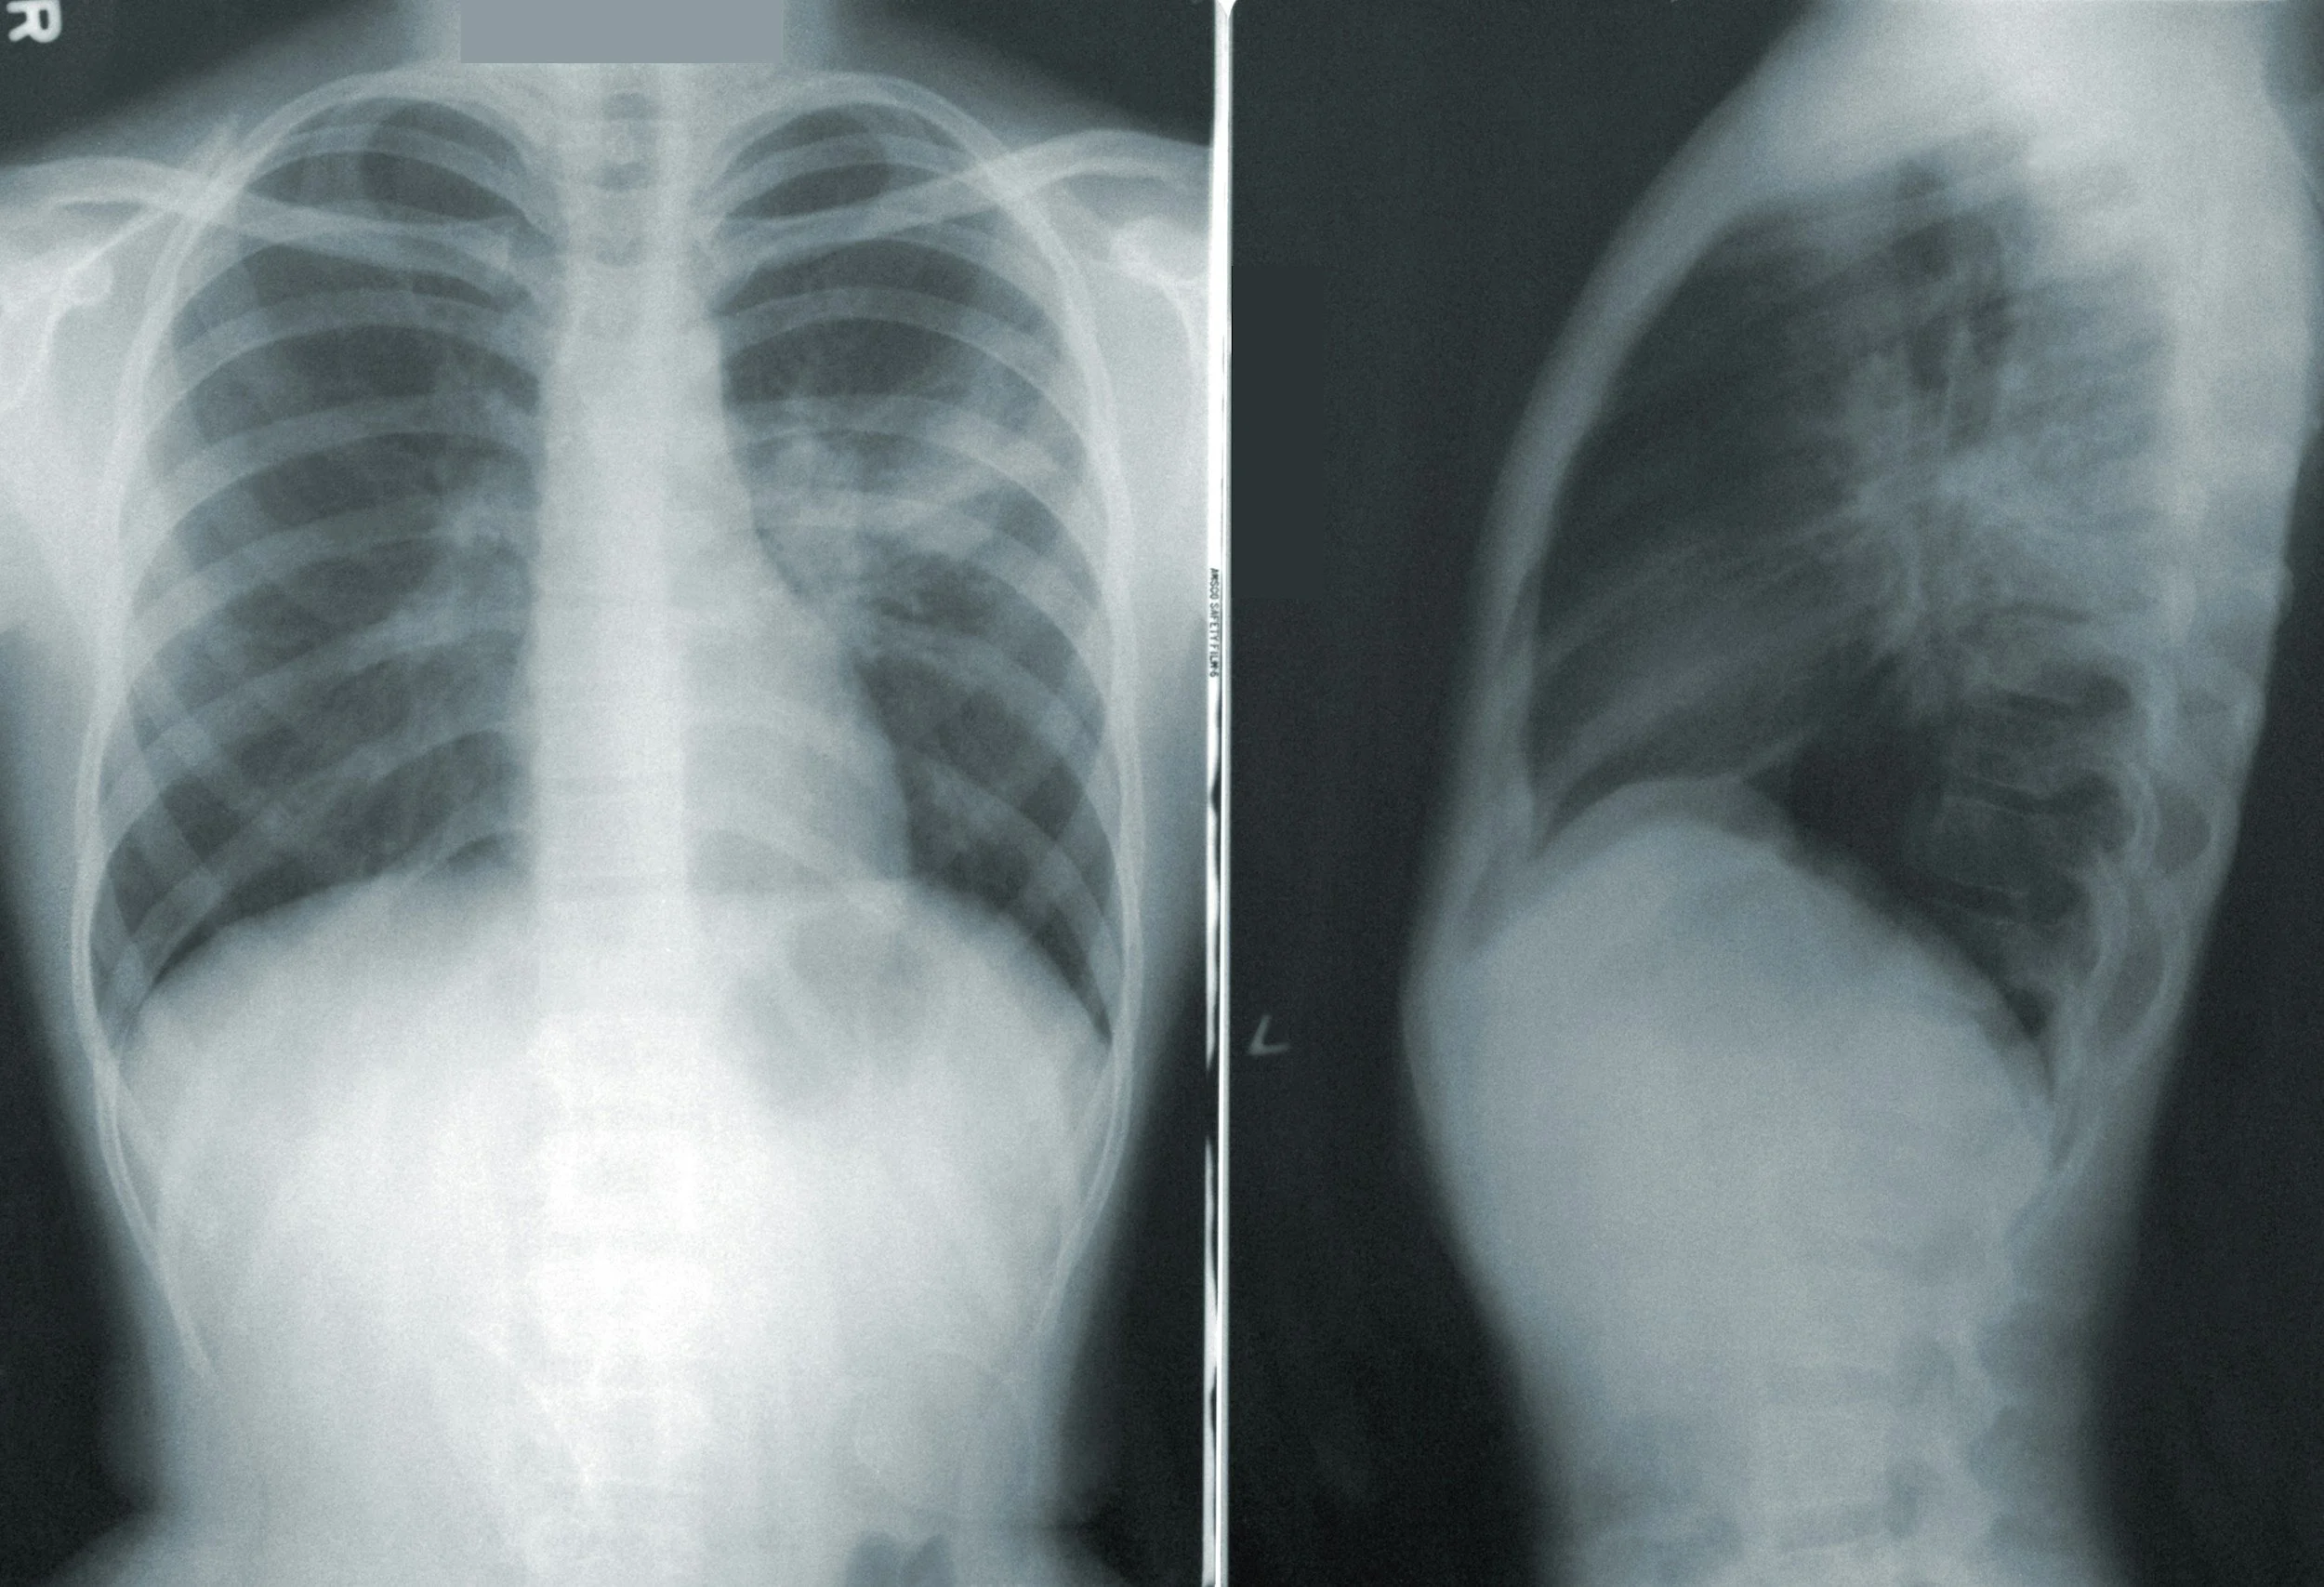

Our X-ray, MRI, Ultrasound and CT services are locally-based near you, providing regional choice for our clients and doctors.

We deliver precision and clarity, through both applied medical imaging and diagnostic expertise; to interpret and report our findings back to your doctor.